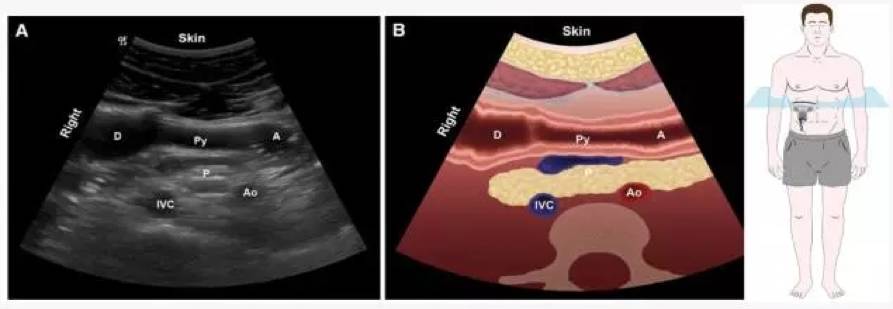

?影像定位:肝左叶、肠系膜上动脉和腹主动脉作为解剖标志

检查平面【1】